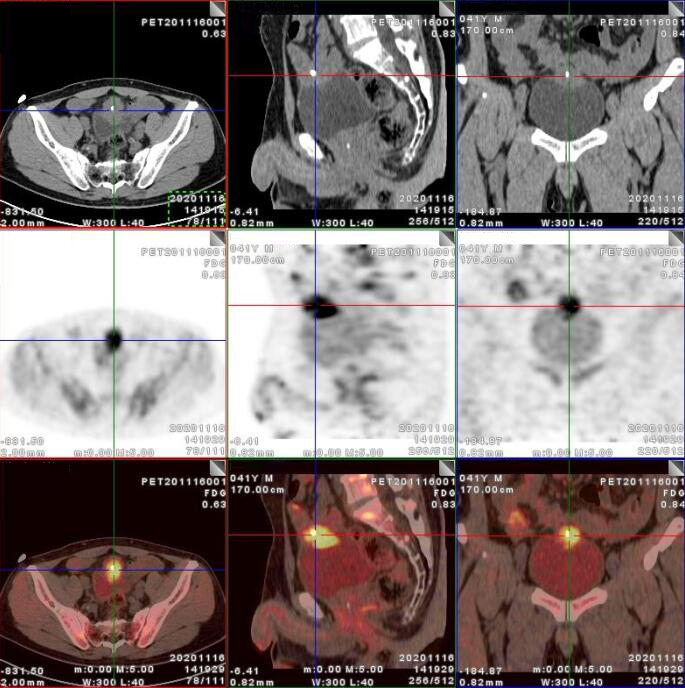

PET/CT影像圖

臍尿管擴(kuò)張,其管壁不均勻增厚,相應(yīng)區(qū)域膀胱頂前壁見一軟組織密度塊影,呈縱向生長(zhǎng),形態(tài)不規(guī)則,大小約3.3x3.8x6.3cm,內(nèi)見斑點(diǎn)鈣化!

膀胱頂前壁軟組織腫塊,放射性攝取SUV Max4.5

膀胱頂前壁軟組織腫塊,放射性攝取SUV Max4.5,延時(shí)4小時(shí)SUV Max8.3